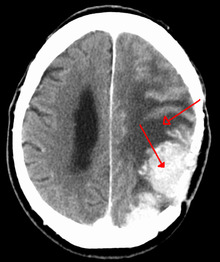

A contrast-enhanced CT scan of the brain, demonstrating the appearance of a meningioma | |

Meningiomas are visualized readily with contrast CT, MRI with gadolinium,[17] and arteriography, all attributed to the fact that meningiomas are extra-axial and vascularized. CSF protein levels are usually found to be elevated when lumbar puncture is used to obtain spinal fluid.